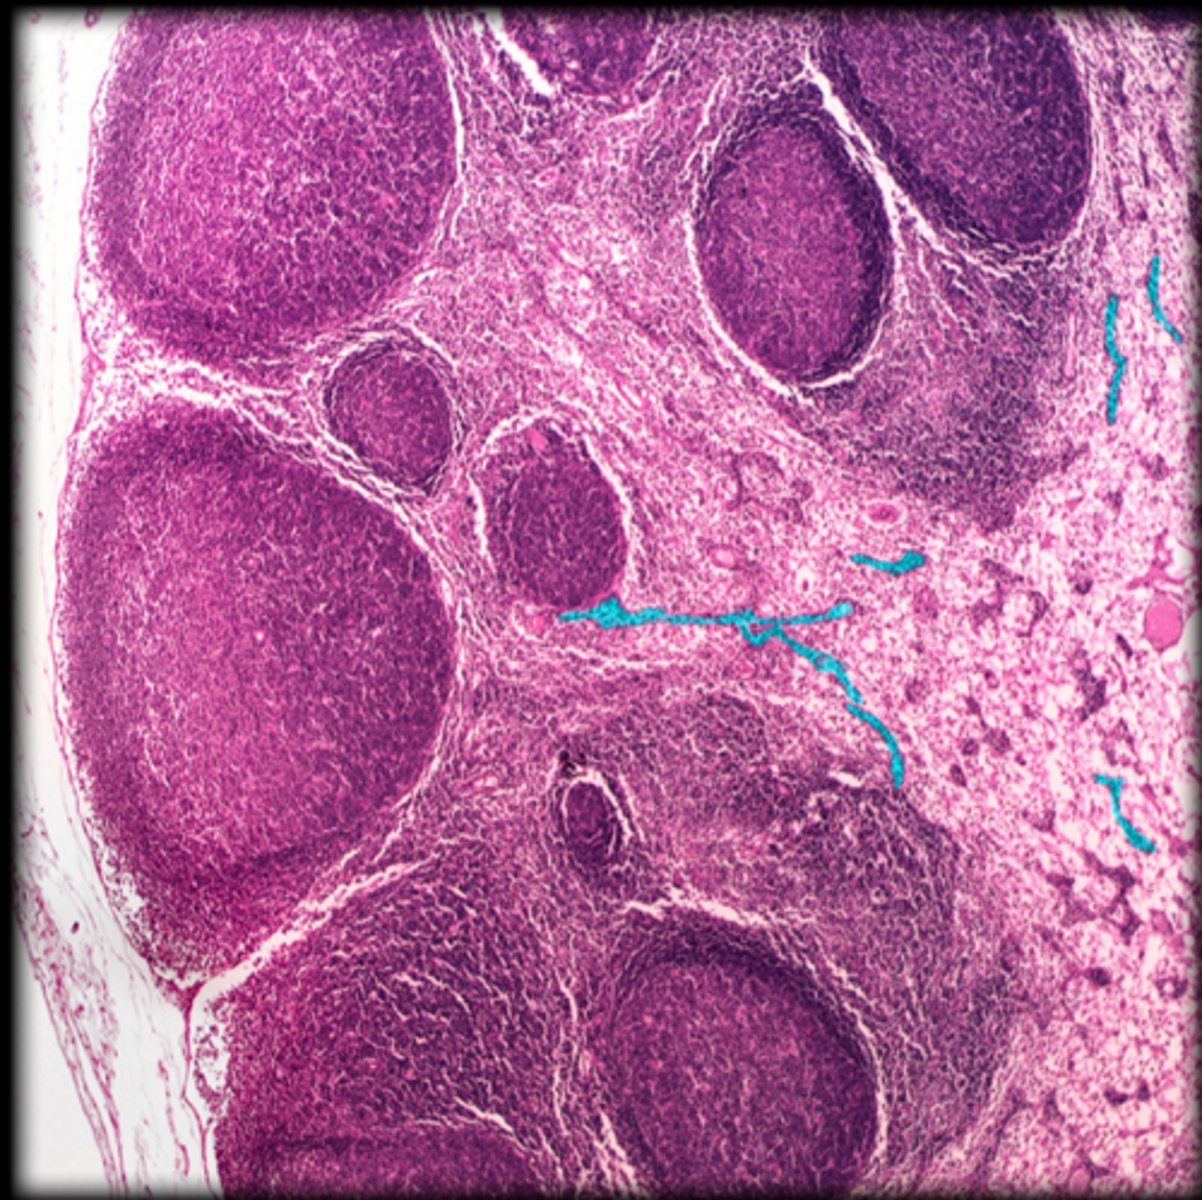

capsule

Lymph node

cortex

medullary cord

medullary sinus